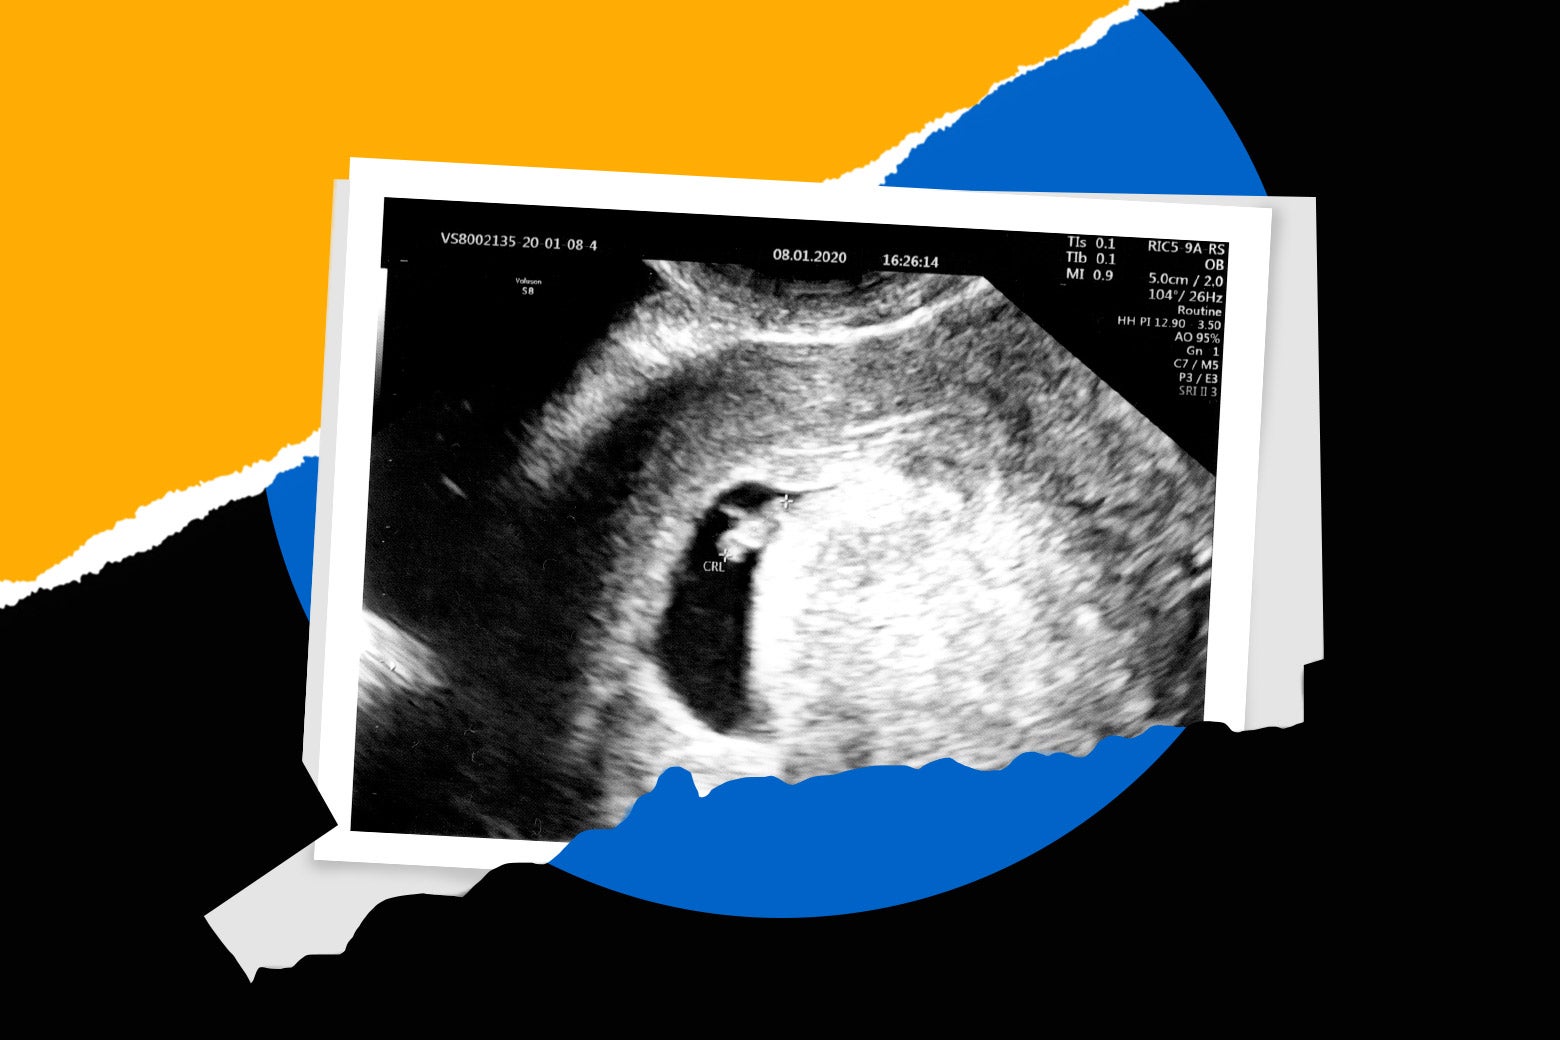

Hence then, the article about how connecticut became an abortion safe haven was published today ( ) and is available on Slate ( Middle East ) The editorial team at PressBee has edited and verified it, and it may have been modified, fully republished, or quoted. You can read and follow the updates of this news or article from its original source.